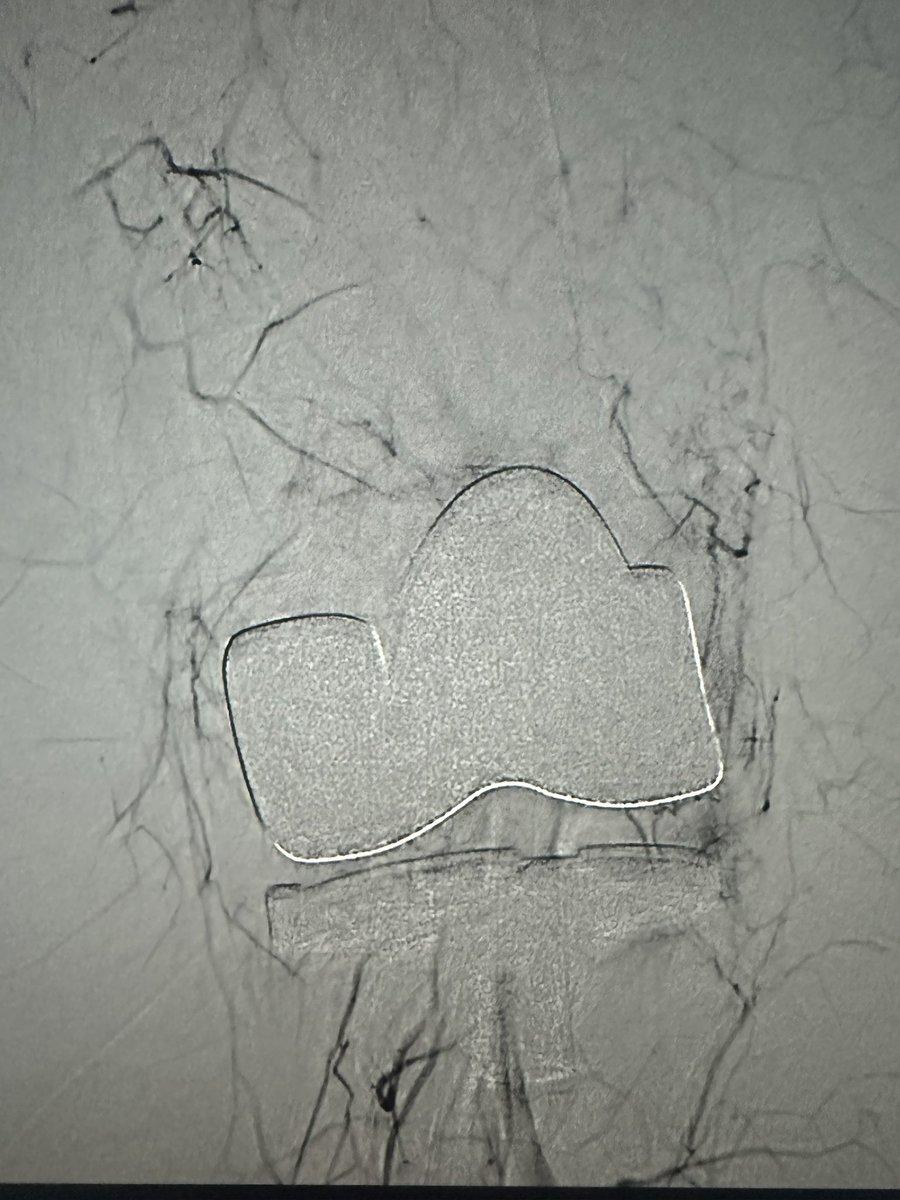

Omar Chohan, DO

Omar Chohan, DO@drochohan·

Bilateral TKR, bilateral knee pain started after left TKR. Left GAE successfully resolved pain in both knees! Patient was incredibly happy to enjoy a walk pain free. #irad #orthopedic @ChengaziMD

Omar Chohan, DO tweet mediaOmar Chohan, DO tweet media